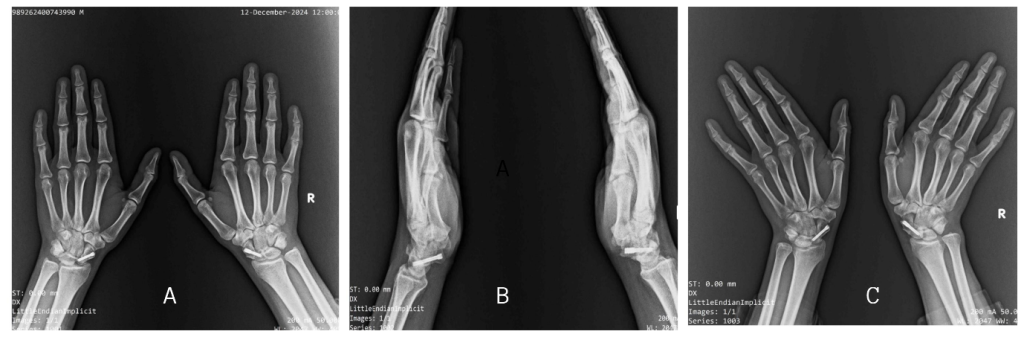

A 12-month follow-up, radiological evaluation using X-rays (Fig. 6), and CT confirmed complete union of the scaphoid fractures. Objective assessment revealed 100% trabecular bridging across the fracture sites in coronal, sagittal, and axial planes (Fig. 7), which is considered the gold standard indicator of union following internal fixation of scaphoid fractures [4]. According to the CT-based grading system, this finding corresponds to Grade 4, indicating complete osseous healing [5]. Furthermore, based on the scaphoid fracture healing score, the patient achieved the maximum score of 10, reflecting optimal bone consolidation and structural integrity [6]. These objective measures provided strong evidence of successful healing, allowing for full return to functional activities.

Figure 6: A 12-month follow-up X-ray of the bilateral wrist. Anteroposterior (a) view, and scaphoid (b) of the bilateral wrist.

Figure 7: A 12-month follow-up computed tomography showing complete bony union of left side axial and sagittal view (a and b), right side axial and sagittal view (c and d), and Coronal view (e).